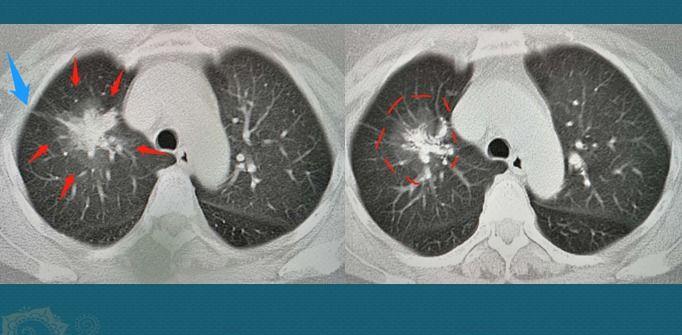

有人会说,肚子疼你跟人看肺部CT,真能滥开检查,不过肺部CT做出来,一个5.2×4.4cm的混合磨玻璃肿瘤:

CT片显示,肿块内部是白色实性成分,形态不规则,肿瘤组织造成了一些支气管的狭窄,外面是一圈半透明的磨玻璃影,边界较清,蓝色箭头显示有胸膜牵拉,符合肺腺癌的特点。

病人还没有出现咳嗽、咳痰、痰中带血等常见的肺癌症状,比较幸运,也没有发生淋巴结转移和远处转移,属于T2N0M0期,有手术机会。